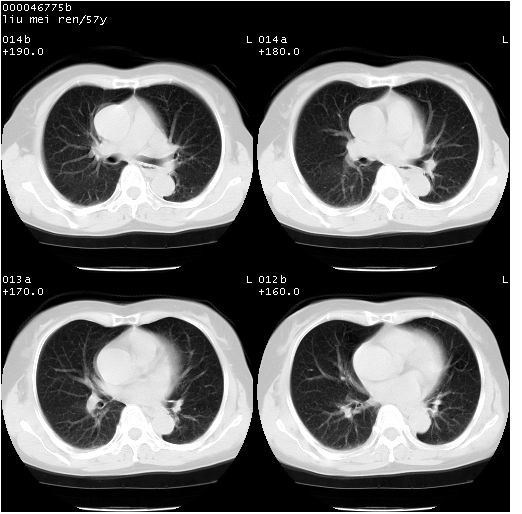

患者 女,57岁。因车祸受伤,其家属要求行“全身ct检查”。平素健康。

胸部ct轴位平扫(层厚10mm,螺距1.5,重建间隔10mm),图像如下:

左位上腔静脉,先天变异。

左位上腔静脉,先天变异。与双侧上腔静脉区别。